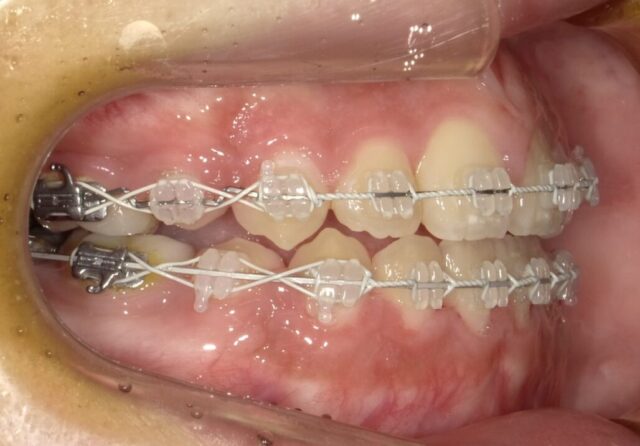

≪右側面観≫

2023年5月

2023年6月

2023年7月

2023年8月

2023年9月

2023年10月

2023年11月

2023年12月

2024年1月

2024年2月

2024年3月

2024年4月

2024年5月

2024年6月

2024年7月

2024年8月

2024年9月

2024年10月

2024年12月

2025年1月